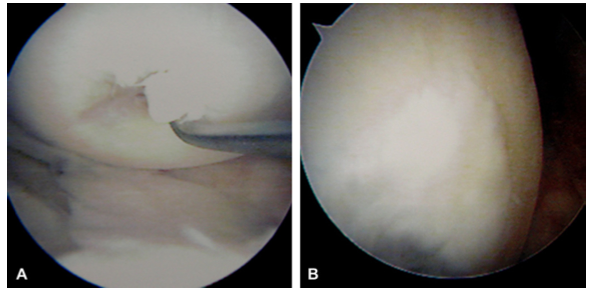

A圖這是一個軟骨損傷的案例,20*30mm的損傷面積,B使用UCF7個月後修復的效果。

A圖看著很恐怖,但是更真實,這就是我們的膝關節的內部,受損嚴重,B 使用UCF修復12個月後的效果